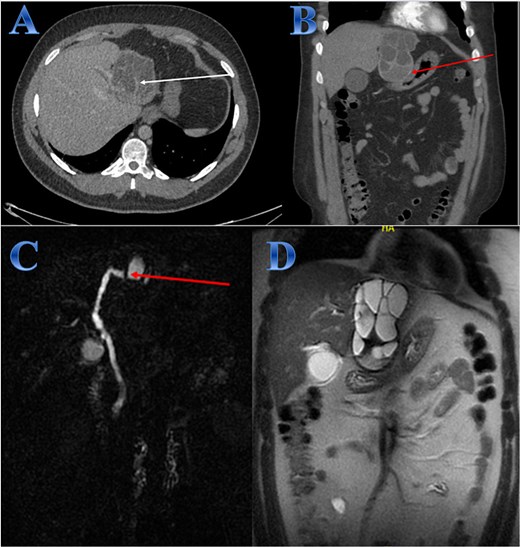

A 42-year-old woman experiences 3 weeks of right upper quadrant pain. On examination showed mild epigastric enlargement and tenderness. Laboratory tests showed eosinophilia, increases in total and direct bilirubin levels. The US discovered a large heterogenous mass with minimal expansion of IHBRs. Abdominal CT revealed large calcified right hepatic lobe cyst with dilated IHBRs (Fig. 1).

Case 1. (A & B) Sagittal and coronal CT cuts of the abdomen at venous phase showing a large peripherally calcified heterogeneous hypodense mass in the right hepatic lobe (photo A), with internal septations and small cysts (daughter cysts), with dilated IHBRs (photo B). (C & D) Coronal MRI images of the abdomen (follow up study) showing biliary extension of the lesion, CBD and the hepatic duct and sub hepatic fluid signal.

A preoperative Albendazole of 400 mg twice daily was started for 8 weeks. An ERCP paired with sphincterotomy, and stenting of the biliary ducts revealed a gelatinous substance with many daughter cysts that came through the ampulla of Vater. The severity of the lesions required an open surgical approach as it is a sizeable CE communicating with common and right hepatic ducts, treated by total peri-cystectomy and closure of the communication with common hepatic duct (CHD) and right hepatic duct (RHD). The cyst was isolated using gauze pads soaked in hypertonic saline. The cyst was punctured with a needle, and its contents were aspirated to reduce intra-cystic pressure. The gall bladder was adherent to the cyst, so cholecystectomy was done; after that, through the cystic duct, contrast material was injected, and it came through two intraparenchymal openings. These two intra-parenchymal openings were closed through deep sutures in two layers. A cholangiogram was done to make sure there was no stenosis or leakage (Fig. 1).